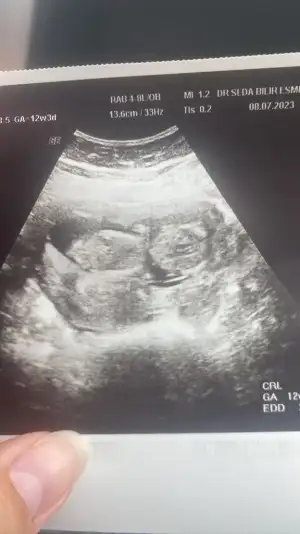

Gebeliklerd3 oluyor bende tansiyon düşüklüğü 6 ya kadar düşerTansiyonunu ölçtün mü, benim de baş ağrım var ama normalde migrenim de var hamileyken daha fazla etkiliyor. Hamilelikte düşük tansiyon iyi diye biliyorum ama hayatı felç edecek duzeydeyse doktoruna bı mesaj at istersen.